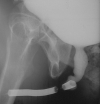

These stents are easy to place under local anaesthesia. The stent should be placed at least 0,5 cm from the external sphincter to avoid urinary incontinence. Stents should not be used in the penile urethra, due to their mobility.

The most frequent complications after stent implant are: incrustations, stones, dislocation, perineal pain, haematuria, incontinence, recurrent urinary tract infection and recurrent stricture. The stricture may locate at the distal or proximal part of the stent or inside the stent due to grow of inflammatory tissue between the links of the stent with obstructive symptoms or urinary retention.

Surgical removal of urethral stent still represents a challenging problem in urology. In some patients, to remove the stent is possible only completely removing the urethra around it. In other patients, the stent is removed link by link, leaving the urethral plate intact. The surgical reconstruction of the urethra, after the stent removal, is performed using a one-stage oral mucosal graft urethroplasty or a staged urethral reconstruction. Anyway, the surgical removal of urethral stent always represents a challenging problem and should be referral to a specialized centre.